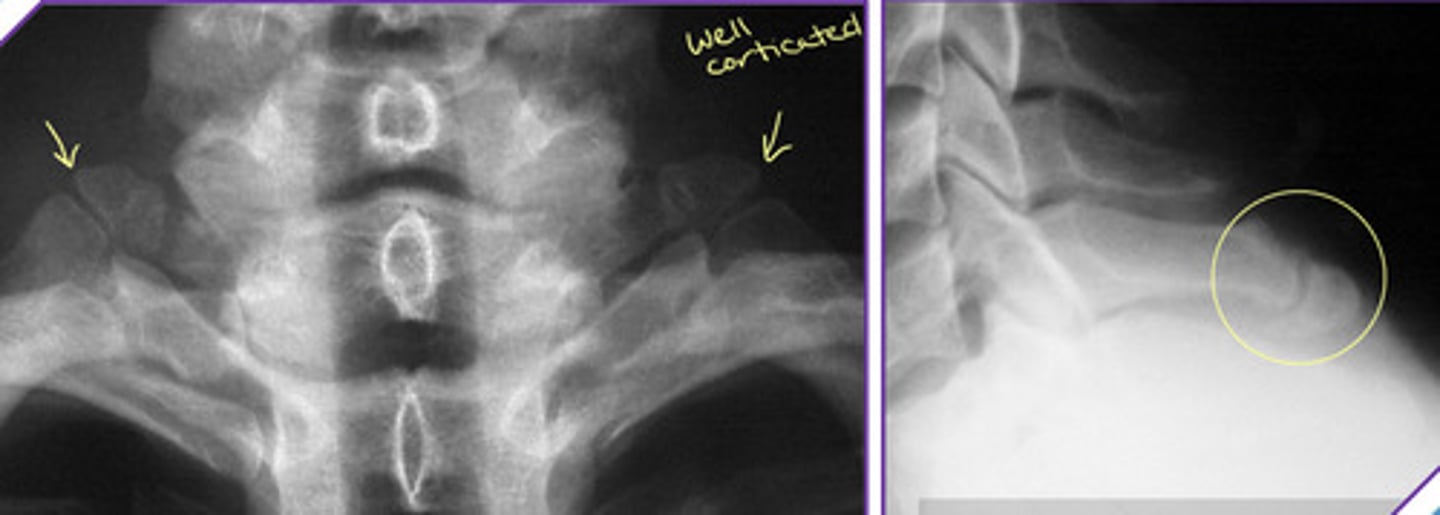

Imaging Findings of Incomplete Segmentation

— Hyperplastic transverse process ("batwing" appearance)

— Hypoplastic disc

— Possible accesory joint formation

— Occasional accessory joint degeneration

Iliolumbar Ligament Calcification

Iliolumbar Ligament Calcification AND a Transitional Segment